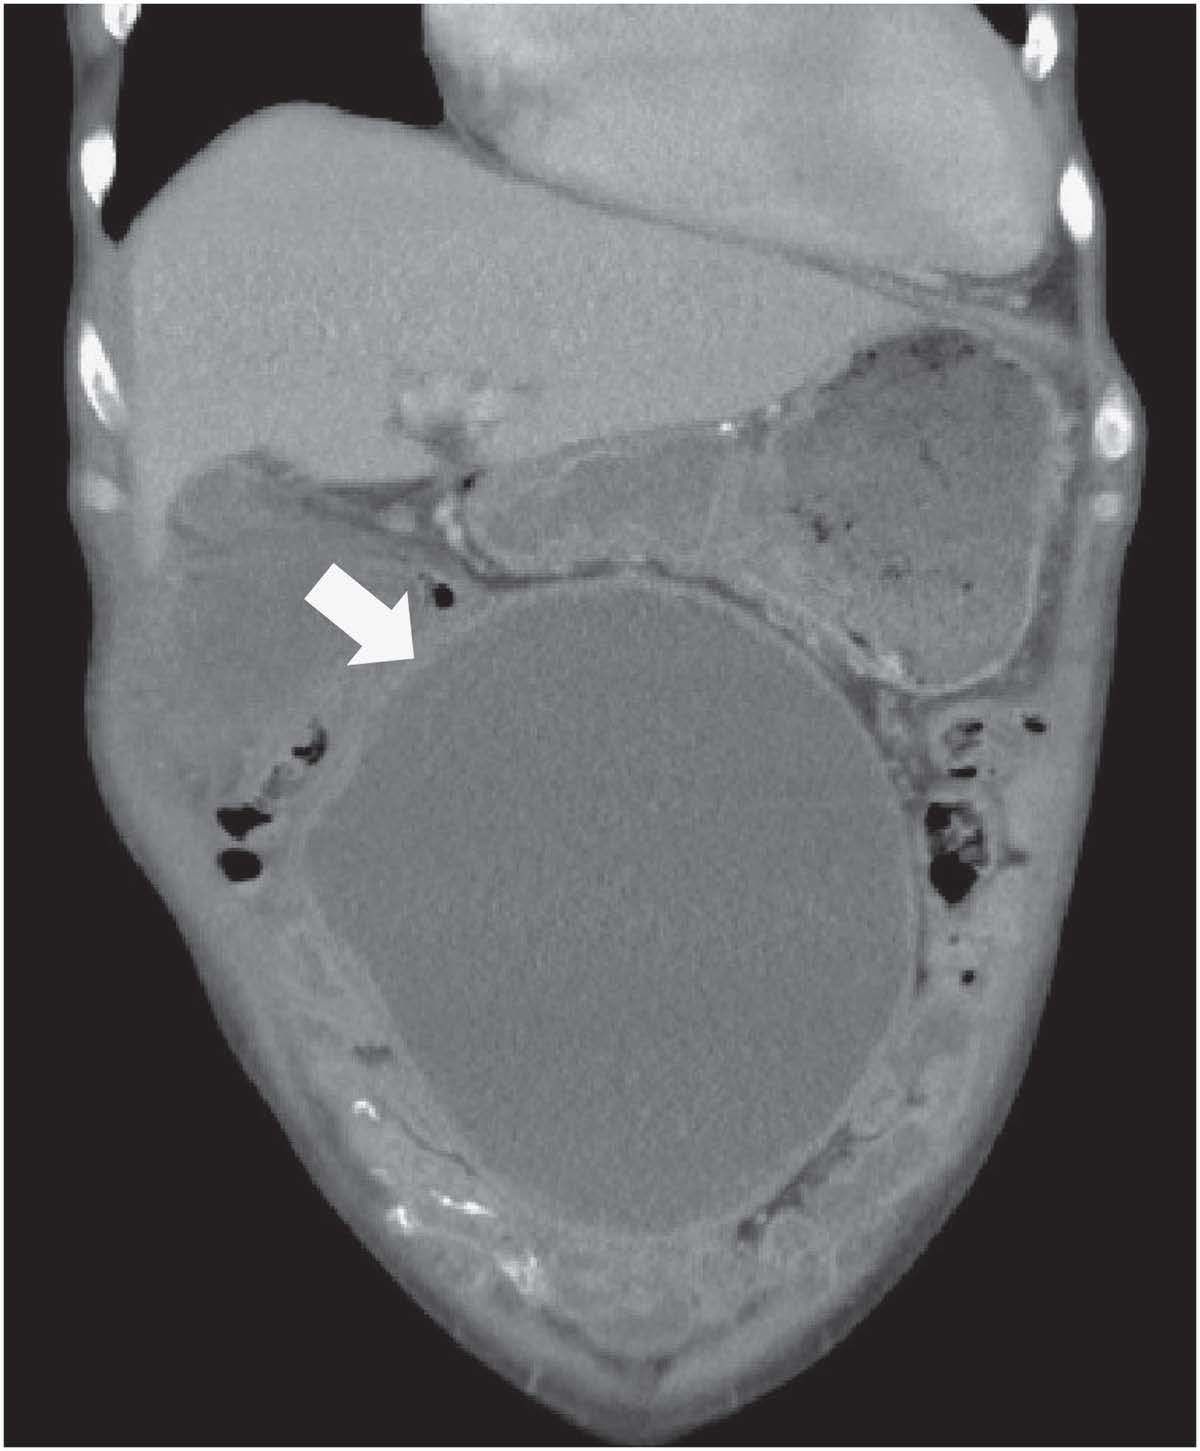

Aft er 3 months of far-infrared therapy, his bowel movement improved. He was able to tolerate a regular oral diet and the color of the dialysate effluent became lightly pink. Because of the improvement in the symptoms aft er far-infrared therapy, our patient decided to follow a conservative treatment plan. Follow-up contrast-enhanced computed tomography scan showed an improvement in dilated loops of small bowel (Figure 3, white arrows). Remarkably, his nutritional status also improved with a significant increase of serum albumin level from 2.7 to 4.2 g/dl, as well as body weight from 59.1 to 62.9 kg aft er far-infrared therapy for 12 months....